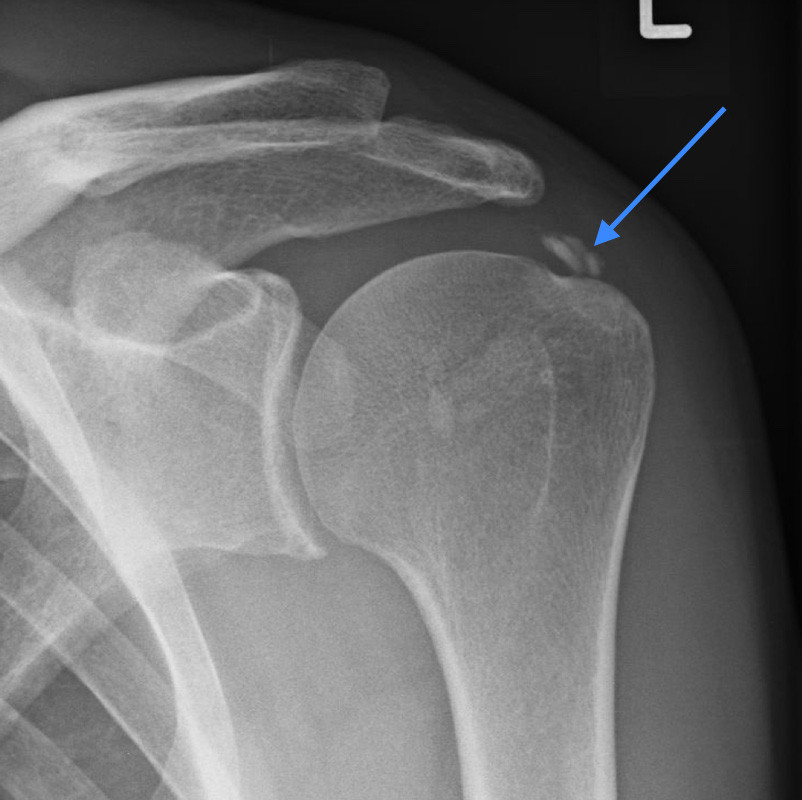

Kalkdepot an der Schulter

Abb. 3: Kalkdepot an der Schulter (Pfeil zeigt auf den Kalkherd)